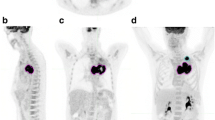

PET/CT images in a 53-year-old woman with adenocarcinoma stage IIIA (T3N1, primary tumour TV in red) illustrating a mismatch between a high decrease in TV and TLG and increasing SUVmax ratios. The baseline (a: coronal view, b: 3D view) and follow-up (c: coronal view, d: 3D view) scans were performed before and after three cycles of induction chemotherapy. SUVmax, TVF and TLGF ratios were respectively 1.25, 0.2 and 0.2. Right upper lobectomy with mediastinal LN dissection was performed. At the most recent follow-up (24 months), the patient was still alive with no evidence of recurrence